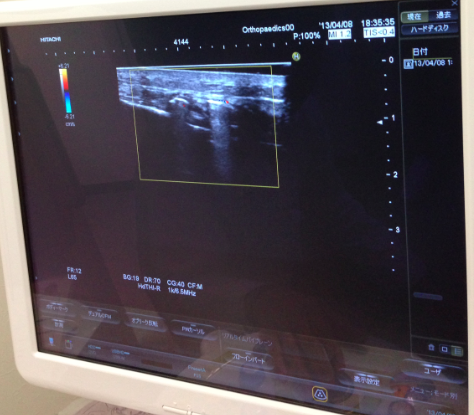

上の写真は、移植したハムストリング腱を固定しているボルトをエコーで確認している様子です。使用機器は、日立メディコの「HI VISION Preirus」。

ボルトの存在は、今では日常生活でほぼ気になりません。ただし今年8月以降に抜釘(ボルト除去)手術を予定しています。それまでに筋力を最大限戻しておくことが重要です。